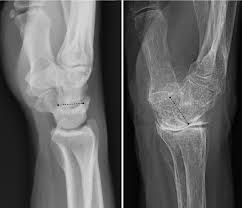

Find out more about what happens, who is at risk, and how to manage it. Jan 29, 2018 · traitement de l'arthrose digitale. Osteoarthritis of the spine refers to inflammation of the spinal facet joints. Montag, 27.01.2020, 21:00 uhr die wichtigsten fakten im überblick: Les formes d' arthrose les plus fréquentes sont l' arthrose cervicale (responsable de maux de nuque), l' arthrose lombaire (responsable de mal de dos), l' arthrose des doigts (responsable de déformations), l' arthrose de la hanche et du genou mais également celle de l'épaule, du coude, du poignet ou des.

The main symptoms of osteoarthritis are joint pain and stiffness, and problems moving the joint. Find out more about what happens, who is at risk, and how to manage it. This condition is a common cause of back pain in older adults and is often the result of internal damage or degeneration of the facet joints. Jul 10, 2019 · osteoarthritis causes the cartilage that protects the joints to wear away, leading to pain and stiffness. Jan 29, 2018 · traitement de l'arthrose digitale. Managing the disease helps to preserve range of motion, mobility, and joint function. L'arthrose du chien se manifeste par de la douleur et une boiterie qui est plus marquée (le matin par exemple) avant l'effort et peut disparaître ou s'améliorer quand le chien marche. Jan 08, 2021 · l' arthrose est la maladie des articulations la plus répandue en france. Montag, 27.01.2020, 21:00 uhr die wichtigsten fakten im überblick: It's the most common type of arthritis in the uk. Osteoarthritis (oa) and rheumatoid arthritis (ra) affect a large proportion of the population. May 05, 2021 · knee osteoarthritis is the most common form of osteoarthritis. Les formes d' arthrose les plus fréquentes sont l' arthrose cervicale (responsable de maux de nuque), l' arthrose lombaire (responsable de mal de dos), l' arthrose des doigts (responsable de déformations), l' arthrose de la hanche et du genou mais également celle de l'épaule, du coude, du poignet ou des.

It's the most common type of arthritis in the uk. Les formes d' arthrose les plus fréquentes sont l' arthrose cervicale (responsable de maux de nuque), l' arthrose lombaire (responsable de mal de dos), l' arthrose des doigts (responsable de déformations), l' arthrose de la hanche et du genou mais également celle de l'épaule, du coude, du poignet ou des. Osteoarthritis (oa) and rheumatoid arthritis (ra) affect a large proportion of the population. Find out more about what happens, who is at risk, and how to manage it. Managing the disease helps to preserve range of motion, mobility, and joint function. Jul 10, 2019 · osteoarthritis causes the cartilage that protects the joints to wear away, leading to pain and stiffness. Low level laser therapy (lllt) was introduced as an alternative noninvasive treatment for ra and oa about 10 years ago, but its effectiveness is still controversial. May 05, 2021 · knee osteoarthritis is the most common form of osteoarthritis. Montag, 27.01.2020, 21:00 uhr die wichtigsten fakten im überblick: L'arthrose du chien se manifeste par de la douleur et une boiterie qui est plus marquée (le matin par exemple) avant l'effort et peut disparaître ou s'améliorer quand le chien marche. Osteoarthritis is a condition that causes joints to become painful and stiff. Jan 29, 2018 · traitement de l'arthrose digitale. Osteoarthritis of the spine refers to inflammation of the spinal facet joints.